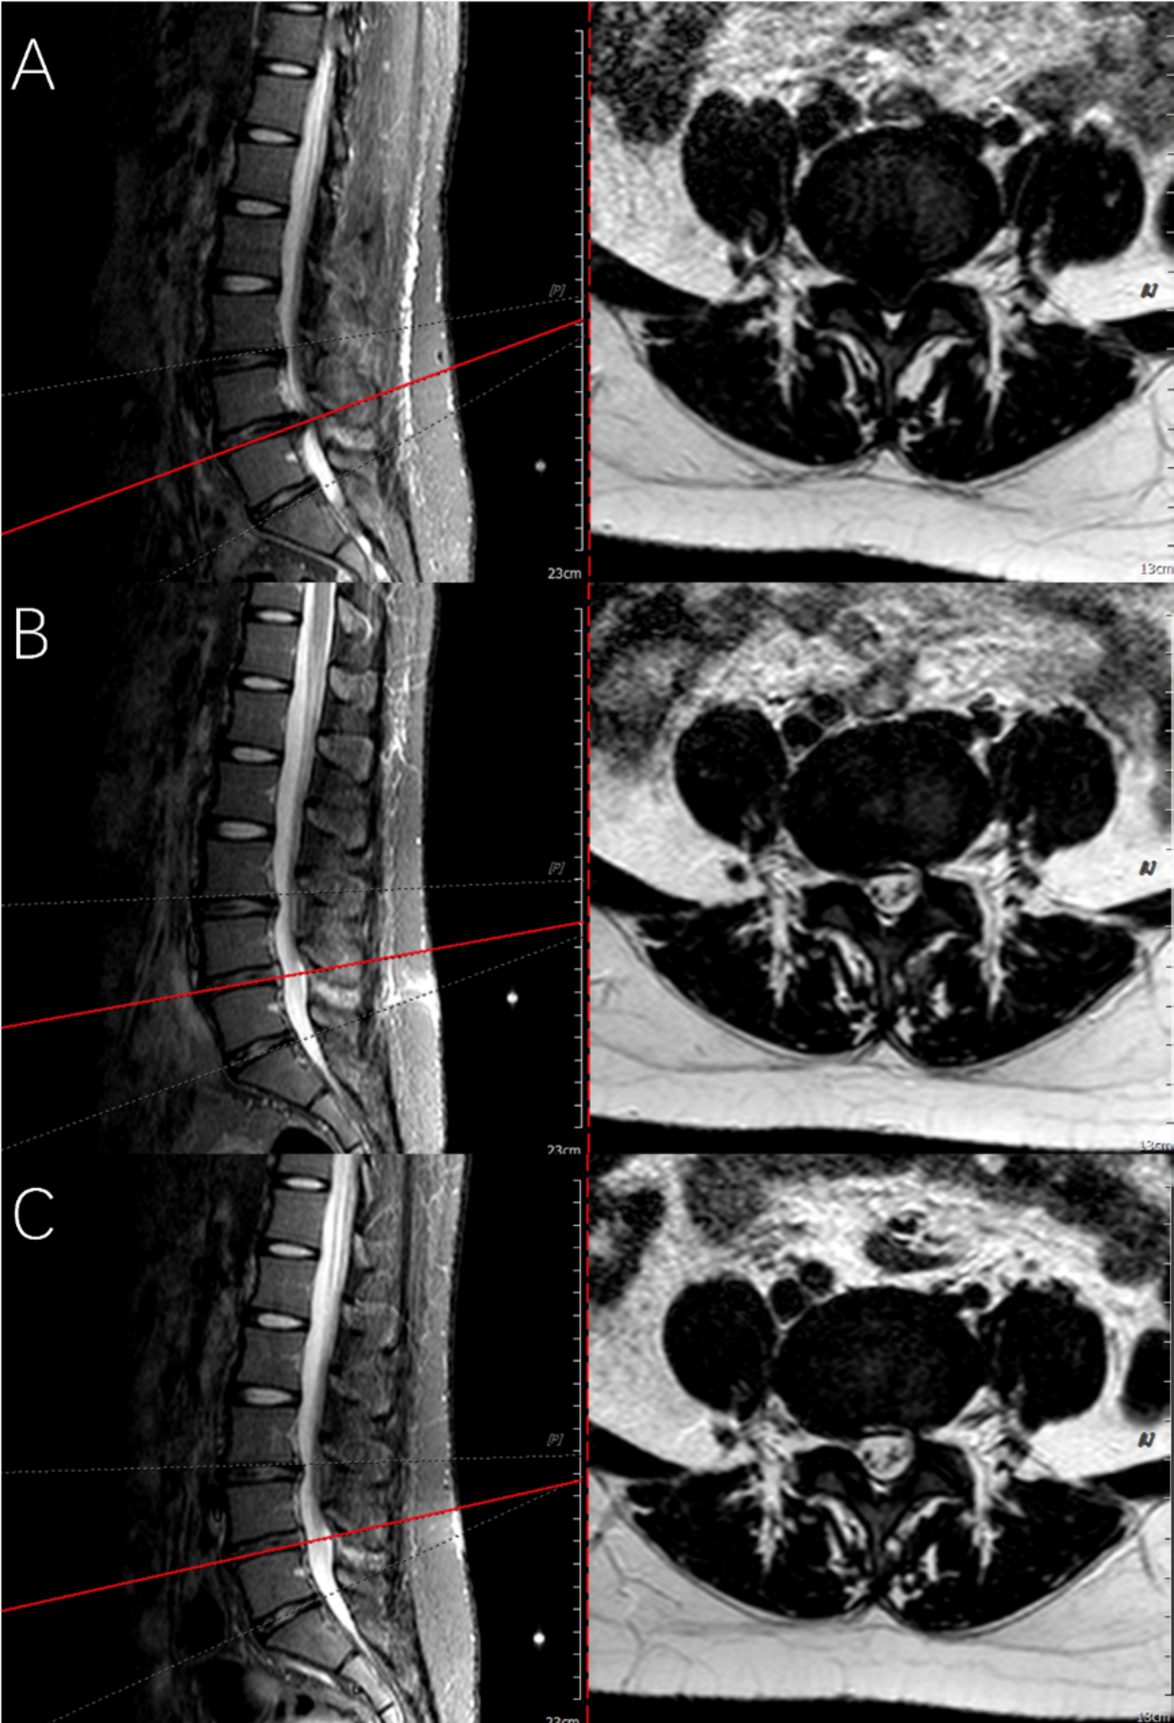

Fig. 6

Preoperative and follow-up lumbar MRIs of the patient using bone-anchor suture technique. (A) Indicates the preoperative sagittal and axial MRIs, showing L4/5 herniation with spinal cord compression. (B) To avoid the artifact signal of spinal cord edema in immediate postoperative MRI examination, MRI re-examined at three-month follow-up indicates the spinal cord and nerve root were decompressed. (C) indicates the lumbar MRIs at one-year follow-up.